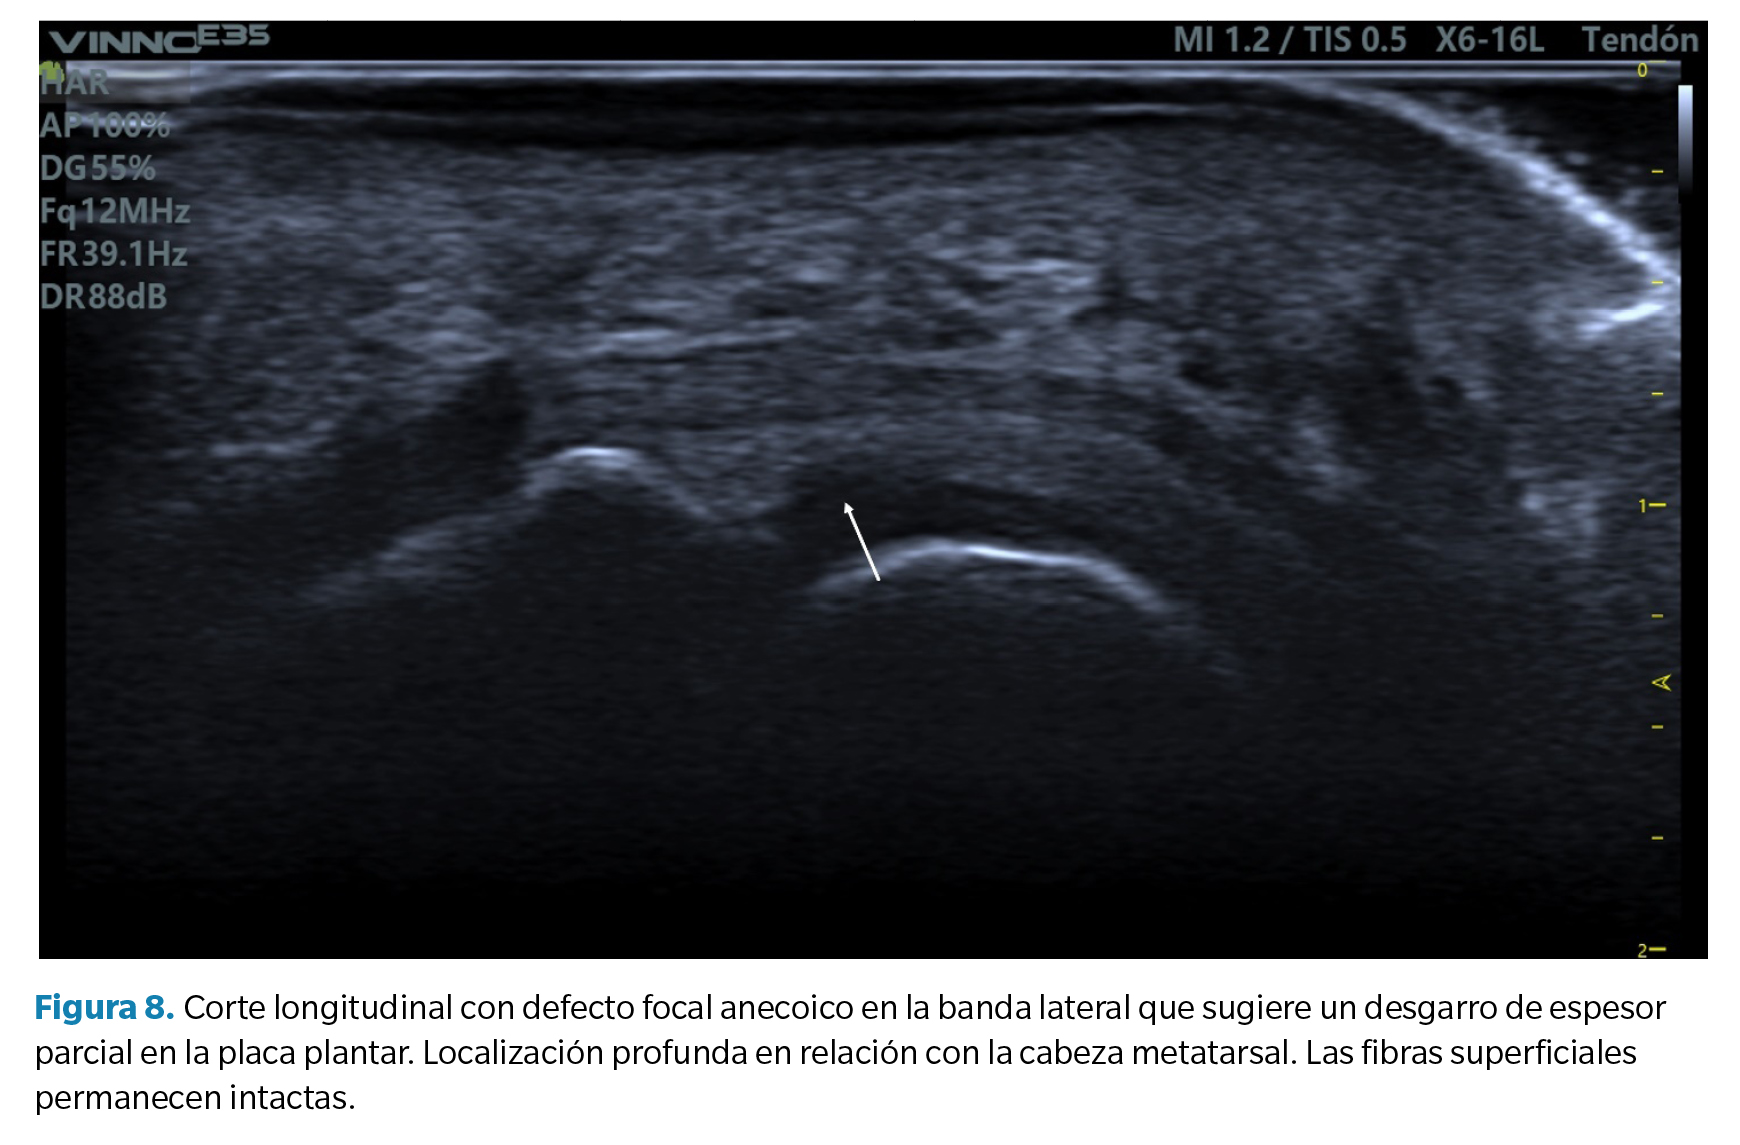

1. Defecto focal anecoico o hipoecoico. Se aprecian como una hendidura discreta en la zona profunda del tejido (zona que articula con la cabeza metatarsal) en su margen lateral. Cuando las fibras superficiales están intactas hablamos de un desgarro de espesor parcial, mientras que cuando dicho desgarro atraviesa todo el tejido hasta su región superficial hablamos de un desgarro de espesor total39 (Figura 8).